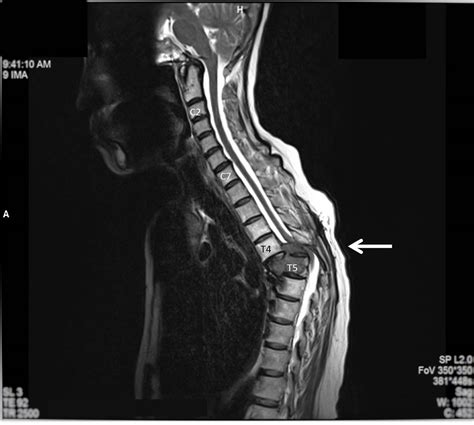

When evaluating mass on spine symptoms, medical professionals typically categorize the growths based on their location. Understanding where the mass resides—whether it is within the spinal canal (intradural) or outside of it (extradural)—is fundamental to determining the cause and the clinical approach.

To differentiate between harmless bumps and more serious conditions, doctors rely on advanced imaging techniques. If you present with mass on spine symptoms, a specialist will likely perform a neurological examination to assess reflexes, strength, and sensory perception. This is usually followed by:

MRI Scan The gold standard for viewing soft tissues, spinal cord, and nerves.